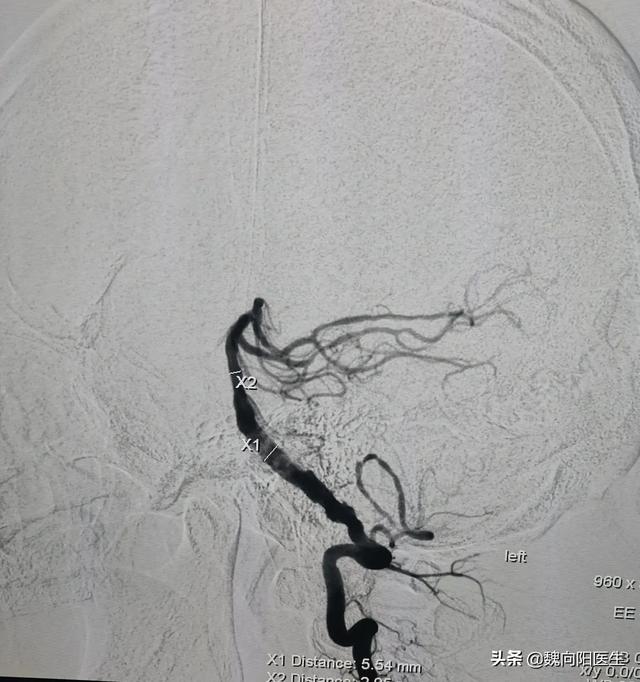

脳への血液供給不足のみが原因で起こるめまいは、通常、後循環虚血としてみられる。通常、椎骨脳底動脈の狭窄や閉塞が小脳虚血の原因となる。重症例では、後循環梗塞に至ることもある。

このような状態では、後循環動脈の狭窄や閉塞を改善し、脳細胞の灌流を改善するために、椎骨脳底動脈バルーン拡張術/ステント留置術を行うために、ほとんどの患者を覚醒させる必要がある。

また、椎骨脳底動脈の動脈硬化を予防するために、高血圧、糖尿病、高脂血症、高ホモシステイン血症などの基礎疾患をコントロールする必要がある。